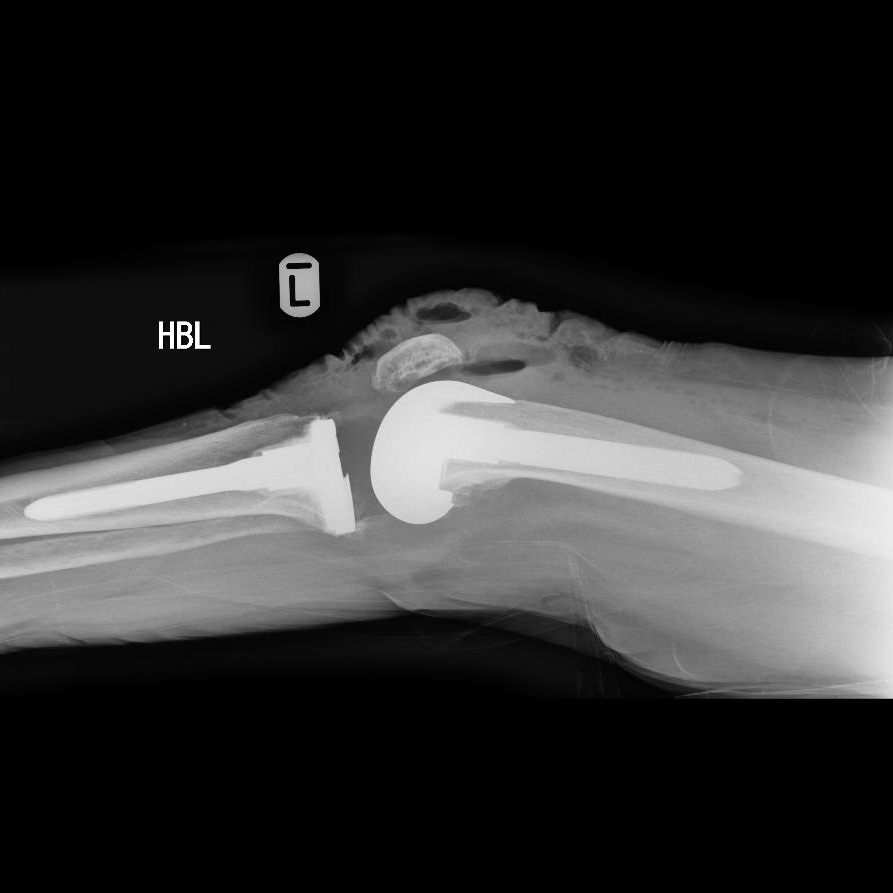

Knee joint implant replacement xray showing in medical orthpodedic What Is Revision Knee Surgery Knee replacement revision surgery restores stability to a worn or damaged knee. Yale medicine orthopedic surgeons discuss when to seek a second opinion. A knee or hip replacement surgery sometimes needs a “redo,” or revision, surgery. Revision surgery is a more intricate procedure than primary knee replacement due to the need to remove the existing prosthesis. Depending on the degree. What Is Revision Knee Surgery.